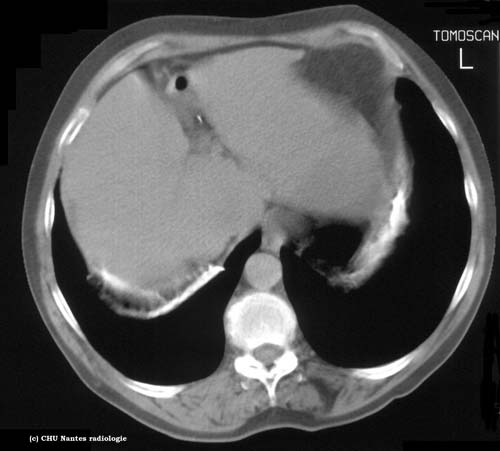

Calcifications pleurales coupe

TDM